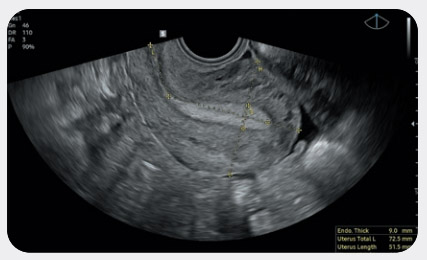

Измерение размера и формы матки с помощью технологии на основе искусственного интеллекта

Функция UterineAssist™, основанная на технологии глубокого обучения, автоматически измеряет размер и форму матки с целью выявления аномалий. Благодаря этому также сокращается длительность сканирования.

В-режим - матка